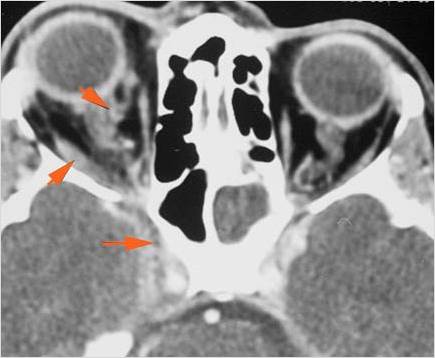

Orbits

The extraconal orbital fat is abnormal. [Yes/No]

There is a subperiosteal abscess or edema along the medial wall, roof or floor of the orbit. [Yes/No]

The extraocular muscles are swollen or otherwise abnormal. [Yes/No]

The intraconal orbital fat is infiltrated. [Yes/No]

The superior and/or inferior ophthalmic veins are dilated or thrombosed. [Yes/No]